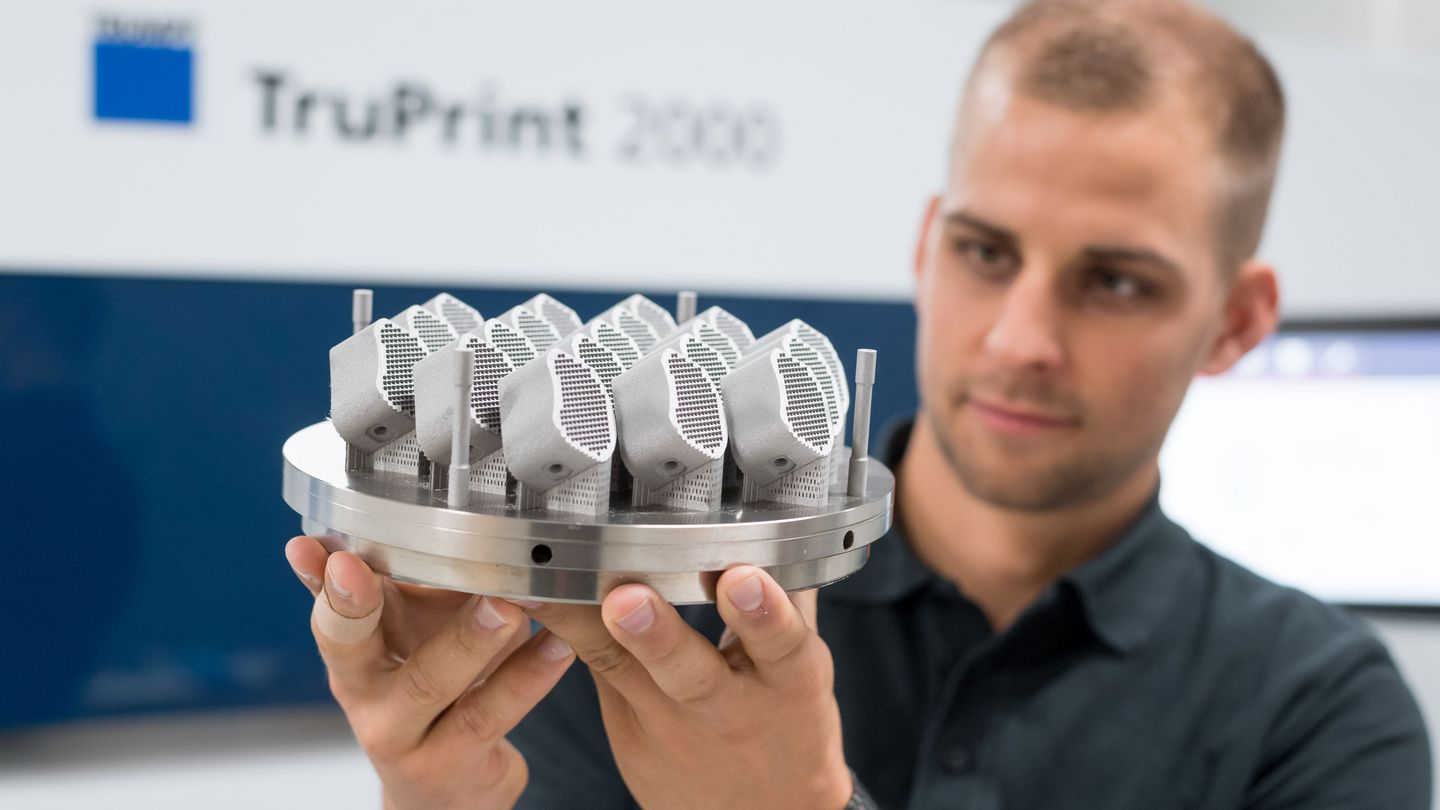

TRUMPF has already used the new machine to print interbody cages, which are implanted to add stability to the spine. These can be inserted as a placeholder between two vertebrae to restore the vertebral segment’s natural height. The lasers’ small focal diameter lends itself to fabricating the implants’ intricate structures. Healthy bone tissue adheres well to these structures. It takes this new system just 24 hours to produce 19 spinal implants. It not only serves medical engineering companies well; it is also an excellent choice for dental applications and tool and mold making. With 300 watts of laser power, it has no trouble handling standard materials such as cobalt-chromium alloys. With that kind of performance, it can readily fabricate dental casts as well as injection-molded parts with complex internal cooling channels. “They provide a more precise way of controlling the temperature of tools during production, which makes them more durable and improves cast parts’ machining quality. This also slashes cycle time for printed tools and boosts productivity.